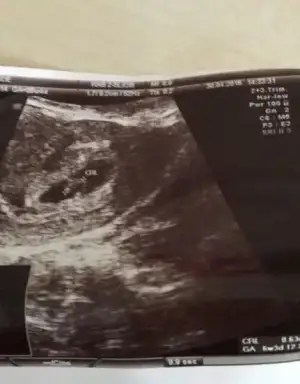

Kızlaaaar arkadaşımın bebeğine tahminde bulunurmusunuzz??

Eki Görüntüle 1893413 Eki Görüntüle 1893413Havalianne__ cim banada yorum yapar misin? Vajinal ultrason

Erkek gibi cnm